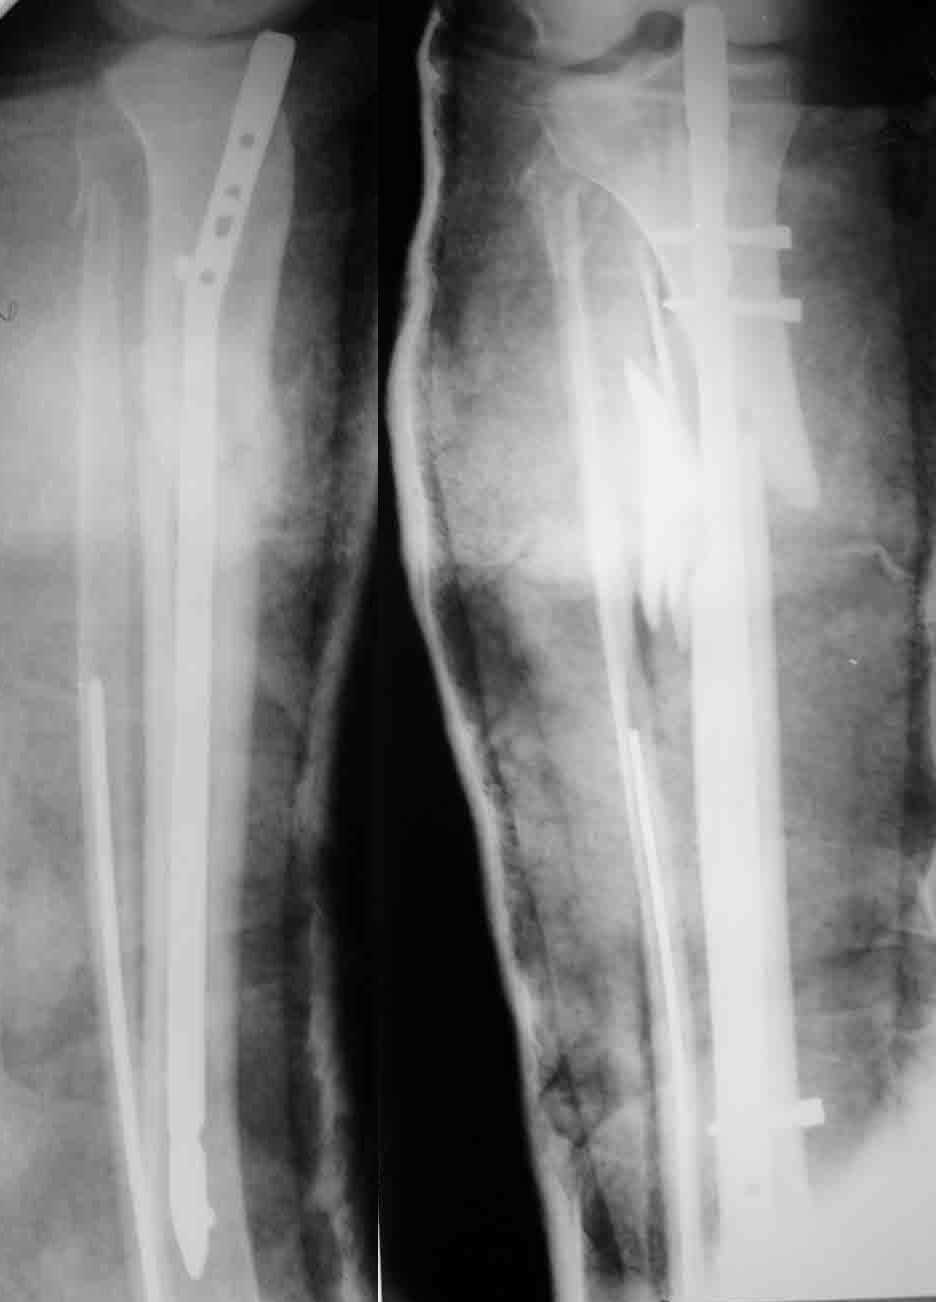

Отправитель: William T Obremskey 20 Декабрь 2003, 12:58

1

2

These can be challenging. I agree w/ all Dr. Carr's points. My preference to prevent the deformity is to use an anteromedial plate. See attached case.

Bill